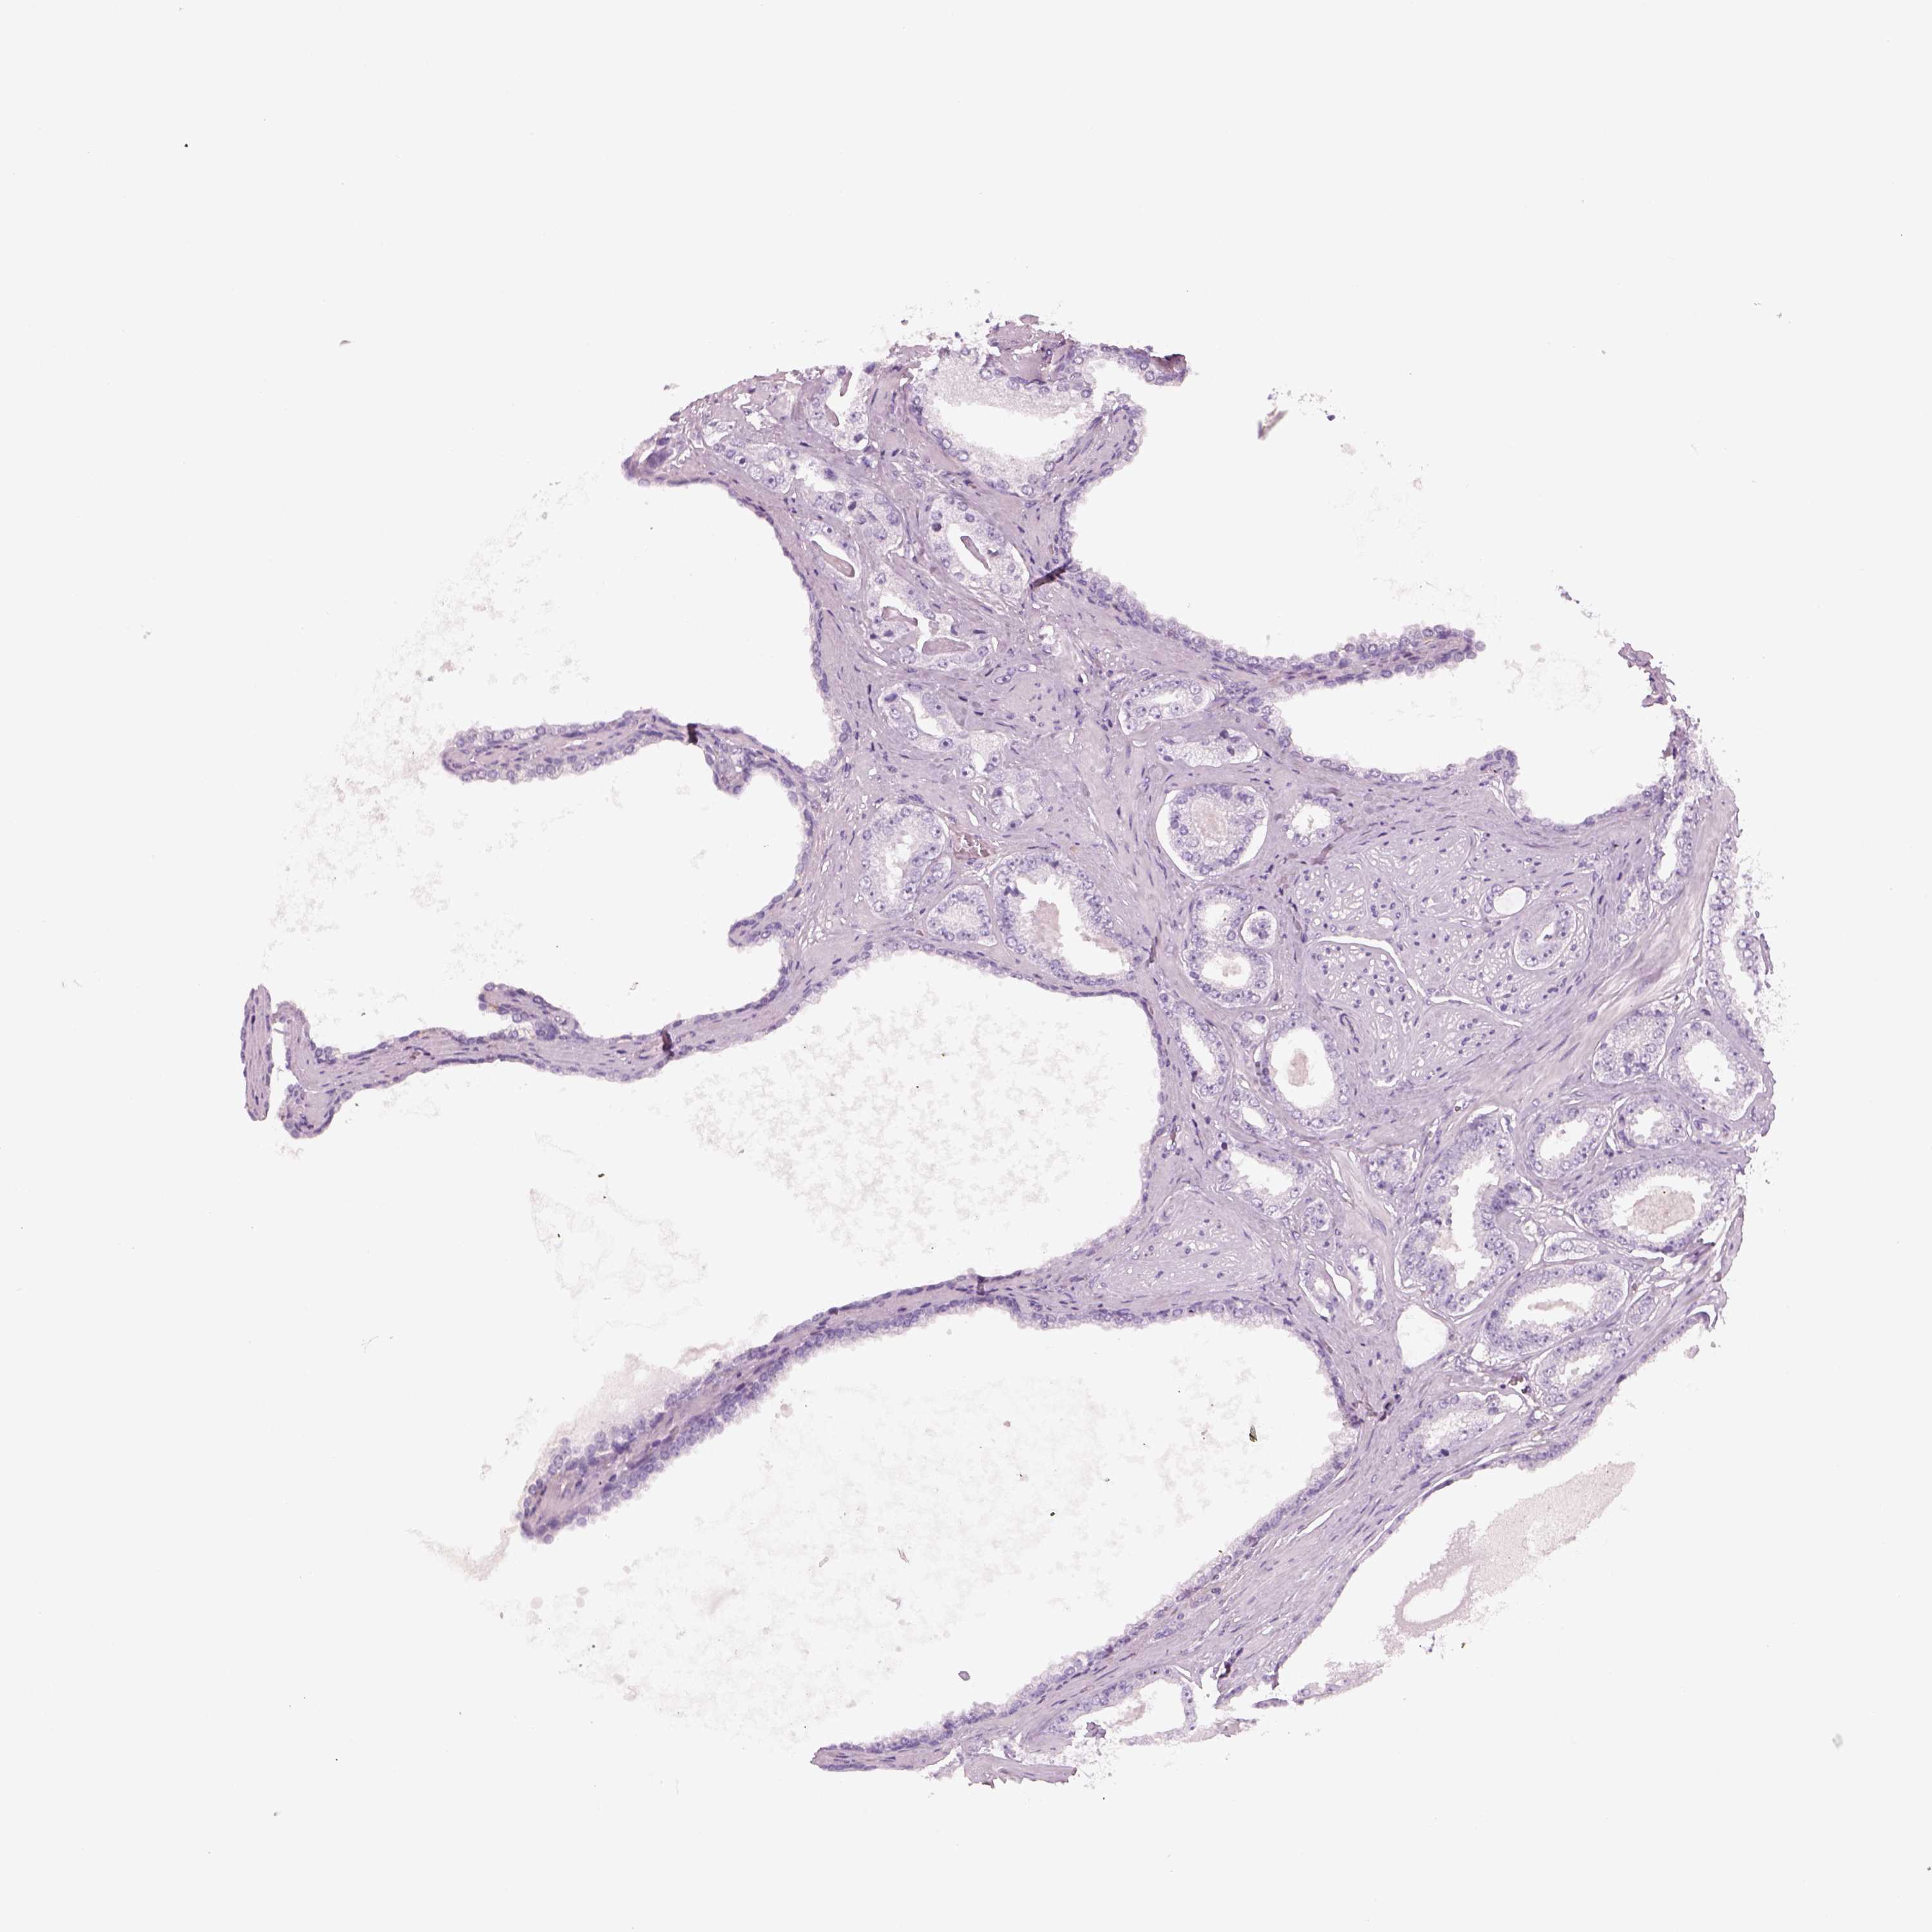

PROSTATE CANCER - Protein expressioni

A mouse-over function shows sample information and annotation data. Click on an image to view it in a full screen mode. Samples can be filtered based on level of antibody staining by selecting one or several of the following categories: high, medium, low and not detected. The assay and annotation is described here.

Note that samples used for immunohistochemistry by the Human Protein Atlas do not correspond to samples in the TCGA dataset.

Antibody stainingi

Antibody staining in the annotated cell types in the current human tissue is reported as not detected, low, medium, or high, based on conventional immunohistochemistry profiling in selected tissues. This score is based on the combination of the staining intensity and fraction of stained cells.

Each image is clickable and will lead to virtual microscopy that enables deeper exploration of all samples and also displays staining intensity scores, fraction scores and subcellular localization as well as patient and tissue information for each sample.

Antibody HPA049124

Staining

High

Medium

Low

Not detected

Intensity

Strong

Moderate

Weak

Negative

Quantity

>75%

75%-25%

<25%

None

Location

Nuclear

Cytoplasmic/membranous

Cytoplasmic/membranous,nuclear

Adenocarcinoma, High grade

Adenocarcinoma, NOS

Adenocarcinoma, Low grade